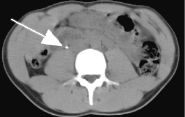

Middle image is a post-contrast delayed image one slice higher showing a dilated ureter (arrow) proximal to the stone mentioned above.